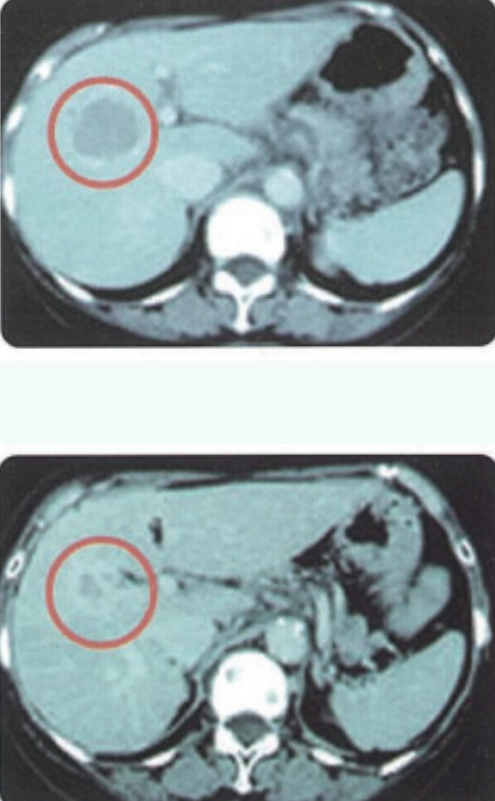

近日,英百瑞分享了一例肺癌患者接受针对Trop-2靶点的ACC-NK细胞疗法实现肿瘤显著缩小93.9%的病例报告。